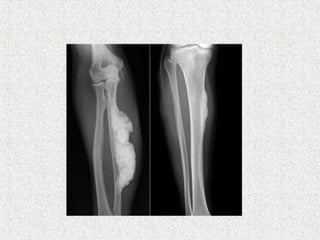

 X rays

 Transverse lucencies/pseudofractures

On the convex surface of weight bearing bone

 Focal bone resorption

 Disorded trabecular pattern

 Expanded bone

 Cortex thick

 Flame shaped/blade of grass osteolytic wedge

 sclerosis

 Pathological #

 A banana fracture

 Complete

 horizontally oriented pathological fracture

 seen in deformed bones affected

  incremental fractures

 A type of insufficiency fracture.

 X rays Transverse lucencies/pseudofractures On the convex surface of weight bearing bone  Focal bone resorption  Disorded trabecular pattern  Expanded bone  Cortex thick  Flame shaped/blade of grass osteolytic wedge  sclerosis  Pathological #

 A banana fracture  Complete  horizontally oriented pathological fracture   seen in deformed bones affected   incremental fractures   A type of insufficiency fracture.